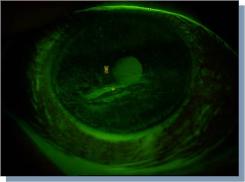

Bij OD is er sprake van een sluitdefect, met als gevolg keratitis e lagophthalmo. Bij

het spleetlamponderzoek valt de ernstige uitdroging van met name de cornea op

(zie fig.) met forse punctata staining en conjunctivale hyperaemie. In het

exposuregebied, waar de oogleden niet sluiten, is zelfs een litteken ontstaan

(figuren hieronder). Bij OS worden geen bijzonderheden aangetroffen.